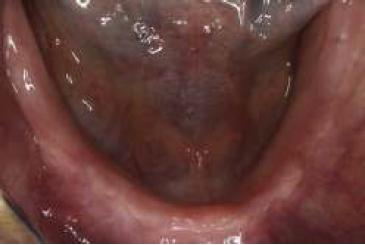

Paciente de sexo femenino, de 72 años de edad al momento del procedimiento. Desdentada total superior e inferior, portadora de prótesis removible total acrílica superior en mal estado. Consulta por la posibilidad de rehabilitar por medio de implantes la zona mandibular (fig. 1), ya que las prótesis convencionales realizadas hasta ese momento carecen de estabilidad. Dentro de la anamnesis la paciente relata estar en tratamiento con medicamentos para la hipertensión.

Imagen preoperatoria donde se observa reborde edéntulo desde una vista oclusal.